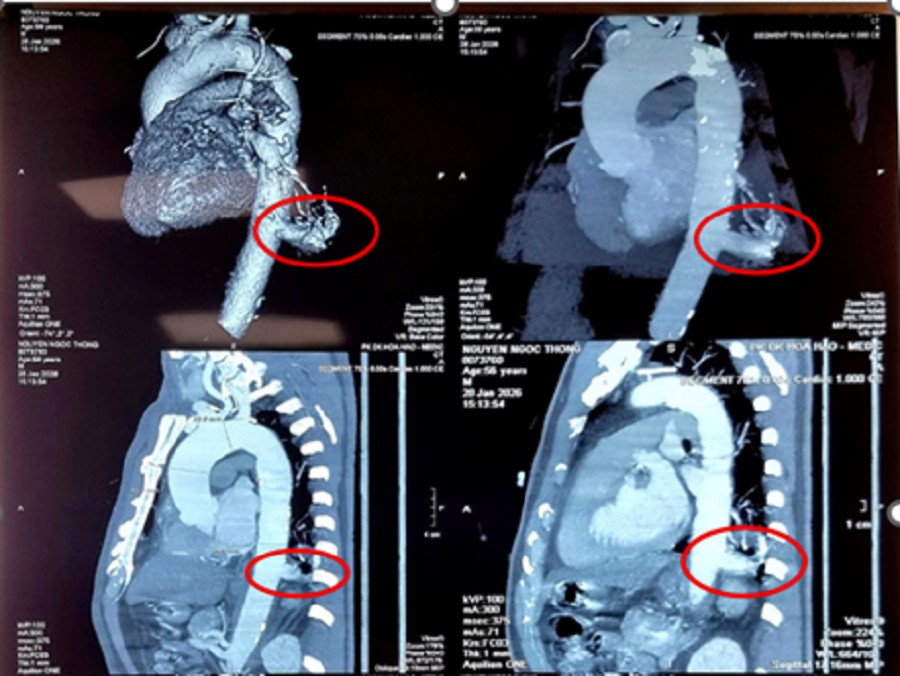

Ngày 3/3, thông tin từ Bệnh viện Bình Dân cho biết, ông N.N.T. (56 tuổi, Tây Ninh) tình cờ phát hiện tổn thương thùy dưới phổi trái trong một lần khám sức khỏe tổng quát. Kết quả chẩn đoán tại bệnh viện xác định ông mắc phổi biệt lập nội thùy – một dị tật bẩm sinh hiếm gặp của phổi. Khối tổn thương có kích thước 23 x 26 mm, nằm ở vị trí thùy dưới phổi trái.

Điều khiến ê kíp đặc biệt lưu ý là nguồn máu nuôi khối biệt lập không xuất phát từ động mạch phổi như cấu trúc sinh lý bình thường, mà nhận máu trực tiếp từ động mạch chủ ngực xuống. Đường kính nhánh động mạch nuôi lên đến 17 mm – kích thước lớn, tiềm ẩn nguy cơ chảy máu ồ ạt nếu xảy ra vỡ mạch trong quá trình bóc tách.

Qua hình ảnh kiểm tra các bác sĩ ghi nhận tình trạng dị dạng bẩm sinh phổi biệt lập nội thùy ở người bệnh